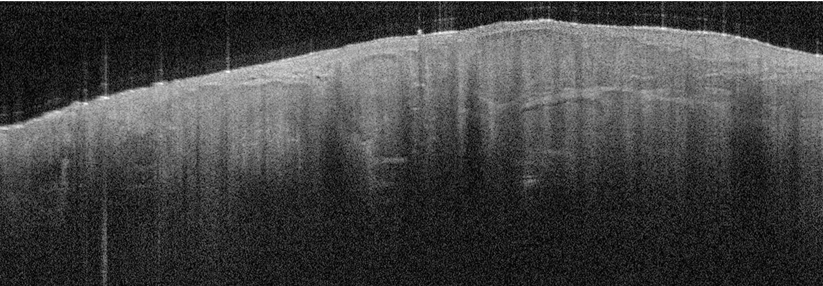

Warum auf die Histologie warten, wenn man mit der optischen Kohärenztomographie auch nicht-invasiv und in Echtzeit in die Haut schauen kann? Mit dem…

Bildgebung

Knotiges Plattenepithelkarzinom bei einer 80-jährigen Frau. © wikimedia/Klaus D. Peter, Gummersbach, Germany (CC BY 2.0 de)

Ulzerierendes Plattenepithelkarzinom bei einem 75-jähringen Mann. © wikimedia/Klaus D. Peter, Wiehl, Germany (CC BY 2.0 de)